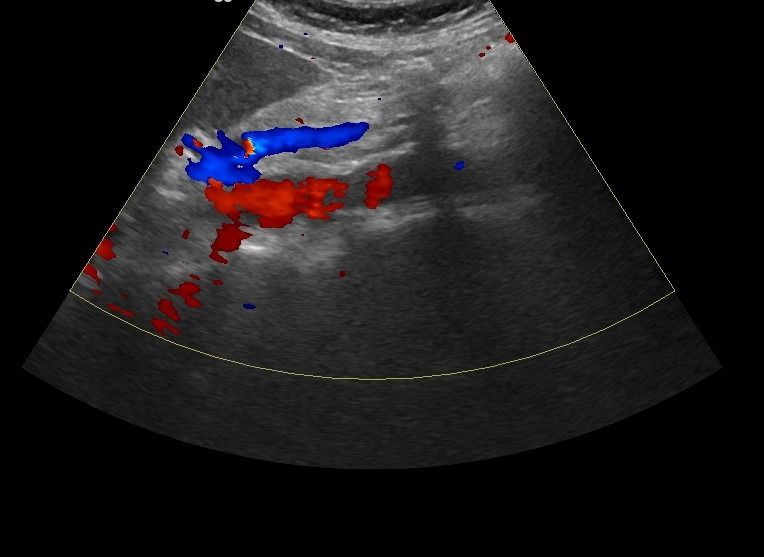

- Αιμοδυναμικές Διαταραχές: Mε τη χρήση του Έγχρωμου και του Παλμικού Doppler μπορούν να μελετηθούν οι ταχύτητες της αιματικής ροής και να ανιχνευθούν πιθανές αιμοδυναμικές διαταραχές.

- Αγγειακή Στένωση: Η αξιολόγηση της αιματικής ροής μπορεί να οδηγήσει στη διάγνωση στένωσης των αγγείων και να υπολογιστεί ο βαθμός της στένωσης.